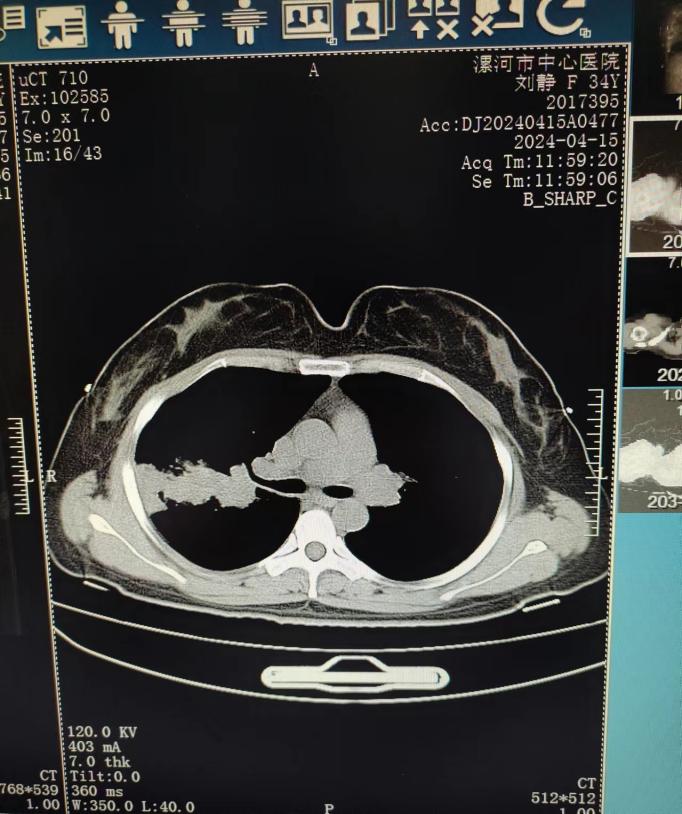

病例:王女士,反复咳嗽、咳痰2年,加重伴喘息2月余。既往曾诊断支气管扩张。曾行肺功能检查提示支气管激发试验阳性。近期于我院住院治疗。胸部CT如下:

因近期再次出现咳嗽、咳痰伴喘息就诊于我院。辅助检查:既往烟曲霉皮肤点刺试验阳性,血清总IgE升高(>2500U/ml),影像学可见指套征、支气管扩张、痰栓,两次外周血嗜酸粒细胞百分比明显升高(1.4-1.5*109/L)升高,支气管镜下可见右上叶及右中叶大量痰栓,BALF NGS提示黄曲霉,变应性支气管肺曲霉病(ABPA)诊断明确。给予针对性治疗数日,韩女士的症状改善后出院。